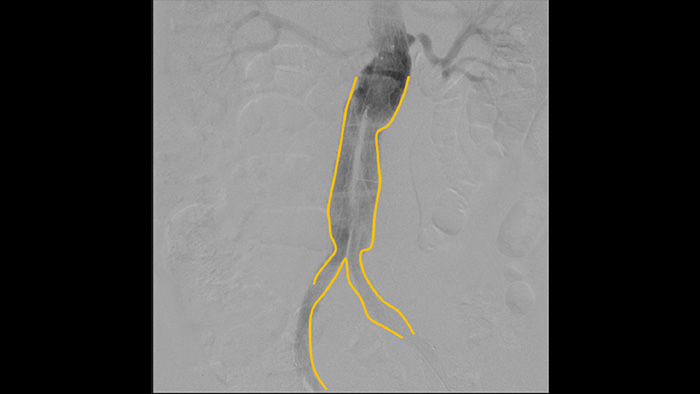

Используйте инструмент для контуринга, чтобы с легкостью отметить бифуркацию или боковые ответвления, рисуя на мониторе передвижной станции просмотра пальцем или подключенной к устройству мышью.

Цифровая субтракционная ангиография (DSA) используется в интервенционных сосудистых процедурах для четкой визуализации кровеносных сосудов путем удаления структур, которые могут снижать видимость сосудов. В рамках рентгеноскопии с картой сосудов ранее полученное субтракционное изображение с контрастированием накладывается на полученное рентгеноскопическое изображение в режиме реального времени, что позволяет отслеживать устройство без повторного введения контраста.